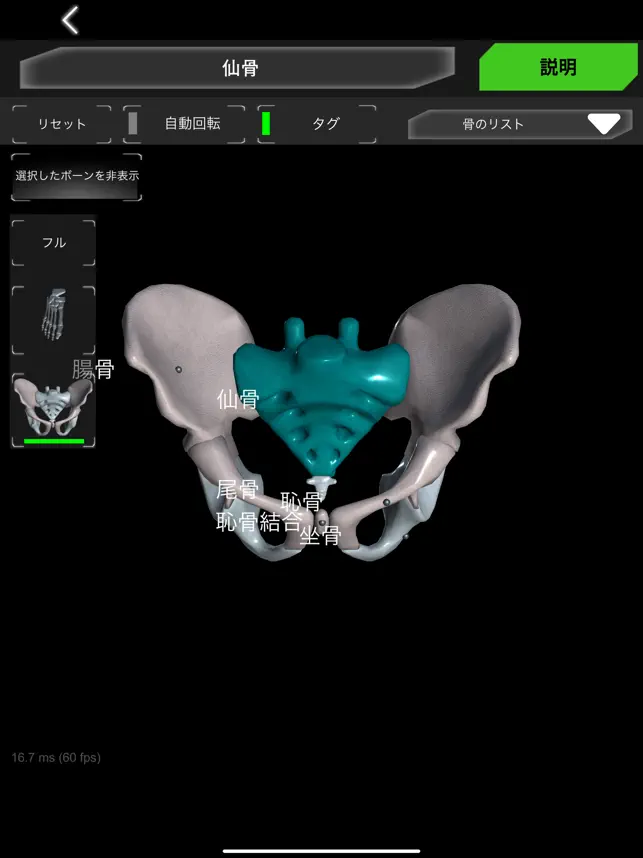

人間の骨格の解剖学に関する情報を 3 次元モデルで示します。

骨システムの 3 次元モデルとそれらすべての説明が表示されます。

頭蓋骨、背骨、肋骨、胸骨、大腿骨、脛骨、腓骨などの各骨を触るとその情報が表示されます。